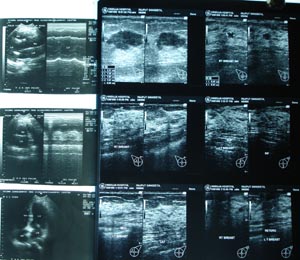

USG.Breast

The USG is performed with hight frequency (7-10 MHZ) probe. The information is to be correlated with mammography finding.